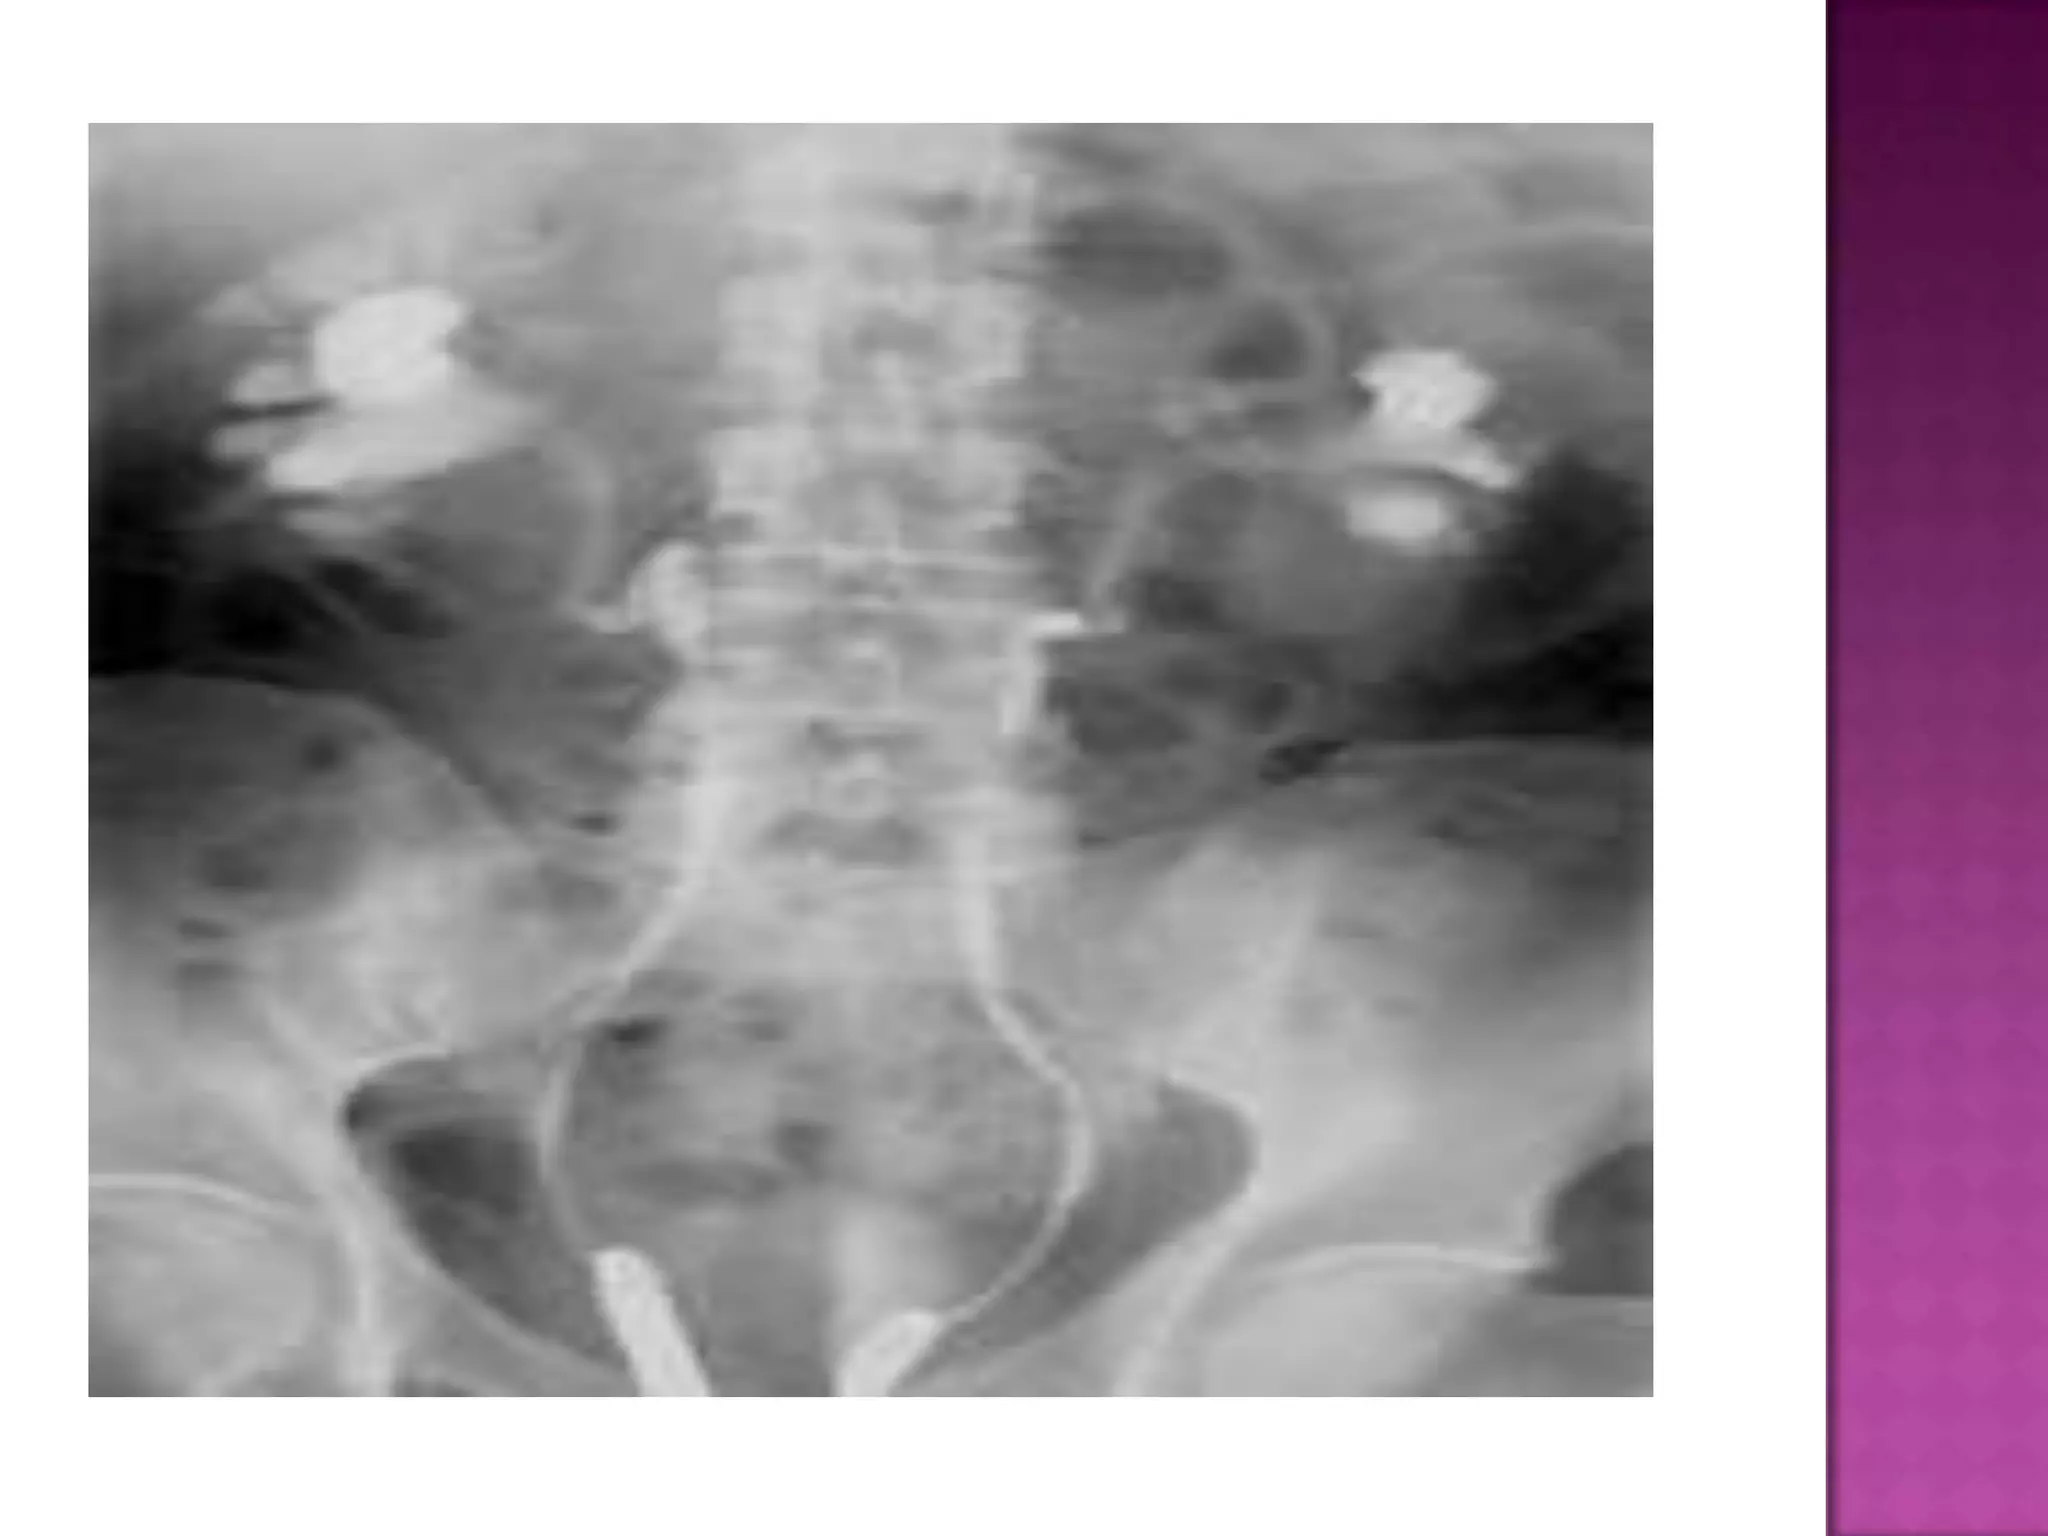

50yrs female,

known diabetic

presented with

lethargy, fever

with chills and

rigors. Urine

examination

shows multiple

pus cells and

ESR is

elevatedabnor

mal gas in the

left renal

region